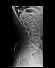

Patient's name:

Maria Fernanda

PAT006921

ACCNO007055

Modality:

CR

1 - unnamed

1 image

2 - unnamed

4 - unnamed